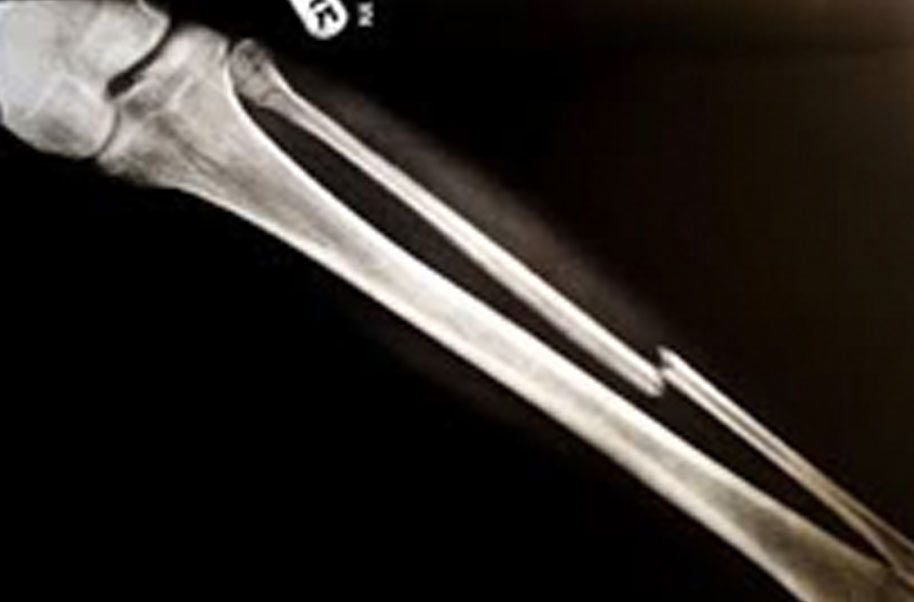

Tail Bone (Broken Bone)

A complete or partial break in a bone.

- Treatment often involves resetting the bone in place and immobilising it in a cast or splint to give it time to heal. Sometimes, surgery with rods, plates and screws may be required.

Causes of bone fractures include trauma, overuse and diseases that weaken bones.